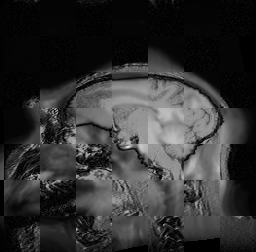

For each of the 10 subjects, we show checkerboard slices in each direction (1) before registration, first row; (2) after rigid->scaleversor->affine registration, second row; and (3) after BSpline registration, third row.

Note the unsuccessful BSpline registration result for Issac.

Issac

Issac is a good example of BSpline registration failure.

Ron noted, the reason might be that Issac had his mouth open, unlike most of the subjects registered successfully.